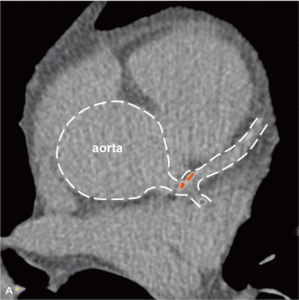

Rycina 4. Progresja zmian miażdżycowych w tętnicach wieńcowych u bezobjawowego chorego z toczniem rumieniowatym układowym w rocznej obserwacji.

Badania obrazowe dowiodły, że mimo stabilnego okresu choroby oraz małej podtrzymującej dawki kortykosteroidów u młodych chorych z SLE miażdżyca tętnic wieńcowych postępuje szybko [33]. Rycina 4 przedstawia progresję zmian miażdżycowych uwidocznioną metodą wielorzędowej tomografii komputerowej, do której doszło u bezobjawowego chorego z SLE w rocznej obserwacji. Duże ryzyko objawowej postaci choroby niedokrwiennej serca obserwowane już u młodych chorych z SLE pozwala przypuszczać, że obecność klasycznych czynników ryzyka miażdżycy nie stanowi w tej grupie głównego mechanizmu patogenetycznego. Zgodnie z oczekiwaniami wykazano brak istotnego wpływu otyłości, nadciśnienia tętniczego, palenia tytoniu, hiperlipidemii lub cukrzycy na obecność i nasilenie zwapnień w tętnicach wieńcowych oraz zaburzeń perfuzji mięśnia serca [24]. Uogólniony proces zapalny, manifestujący się podwyższeniem stężenia białka CRP oraz obniżeniem stężenia składowych C3c i C4 układu dopełniacza, nie wpływa istotnie na rozwój zmian miażdżycowych w młodym wieku [24], chyba że stężenie CRP jest przewlekle istotnie podwyższone i przekracza 20 mg/l [34].